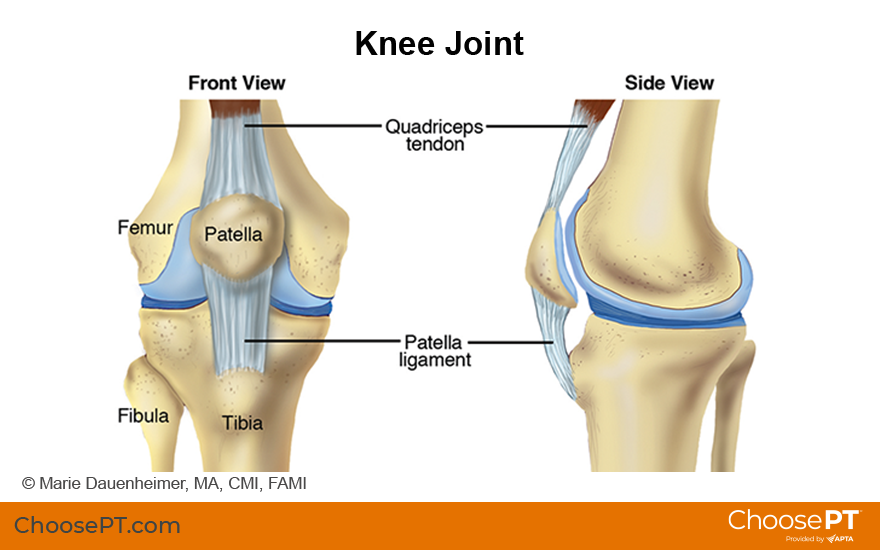

Patellofemoral pain is pain at the front of the knee, under or around the kneecap (patella). PFP is one of the most common types of knee pain experienced in the United States. It often occurs among athletes, active teenagers, older adults, and people who perform physical labor. Patellofemoral pain affects more women than men. It accounts for 20% to 25% of all reported knee pain. Physical therapists design treatment programs for people with PFP to help reduce pain and improve function.

Patellofemoral pain is pain under or around the kneecap, at the front of the knee. PFP may occur after a sudden increase in activities like running or jumping. Research suggests that PFP results from activity levels that are increased faster than the knee can adapt. Other contributing factors to PFP may include: